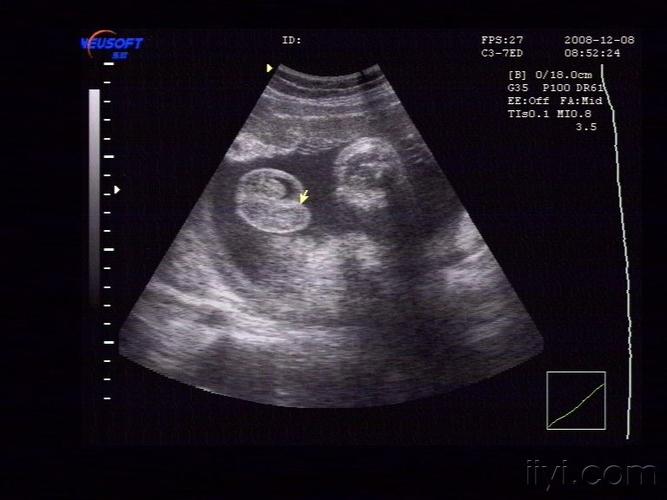

二维超声:胎儿双侧阴囊内可见睾丸回声(图 1).

孕22周男孩睾丸b超图

孕31周男孩睾丸b超图